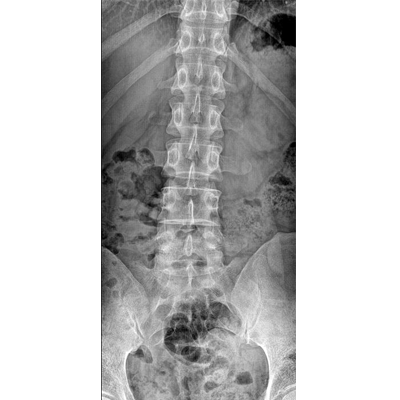

●大尺寸非晶硅平板探測器。

●探測器可以大范圍轉(zhuǎn)動,大尺寸有效探測面積,可滿足人體多部位攝影需求。